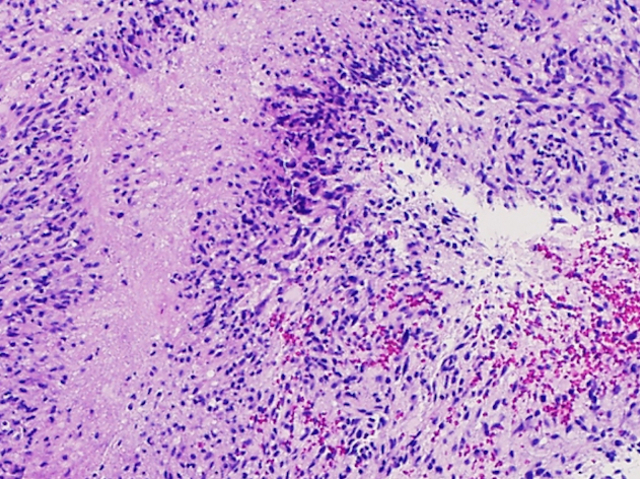

Immortality Kill Switch

This is a deadly glioblastoma brain tumour, seen down a microscope and stained to reveal living (purple) and dying (red) cancer cells. Scientists have long been struggling to understand what makes these cancers so difficult to treat and the search has now led to a gene called TERT, which is the most commonly altered gene in glioblastoma. TERT is an important component of telomerase – the molecular ‘immortality machine’ that maintains DNA so cancer cells can keep dividing. Unfortunately, TERT is also needed by healthy cells so it's hard to target with anti-cancer drugs. But researchers have now found that TERT is activated by another molecule, GABP-beta1L, which isn’t needed by healthy cells but is essential for making cancer cells immortal. Getting rid of GABP-beta1L dramatically slows down the growth of glioblastoma cells in the lab – an approach that could be developed into a potentially powerful treatment in the future.